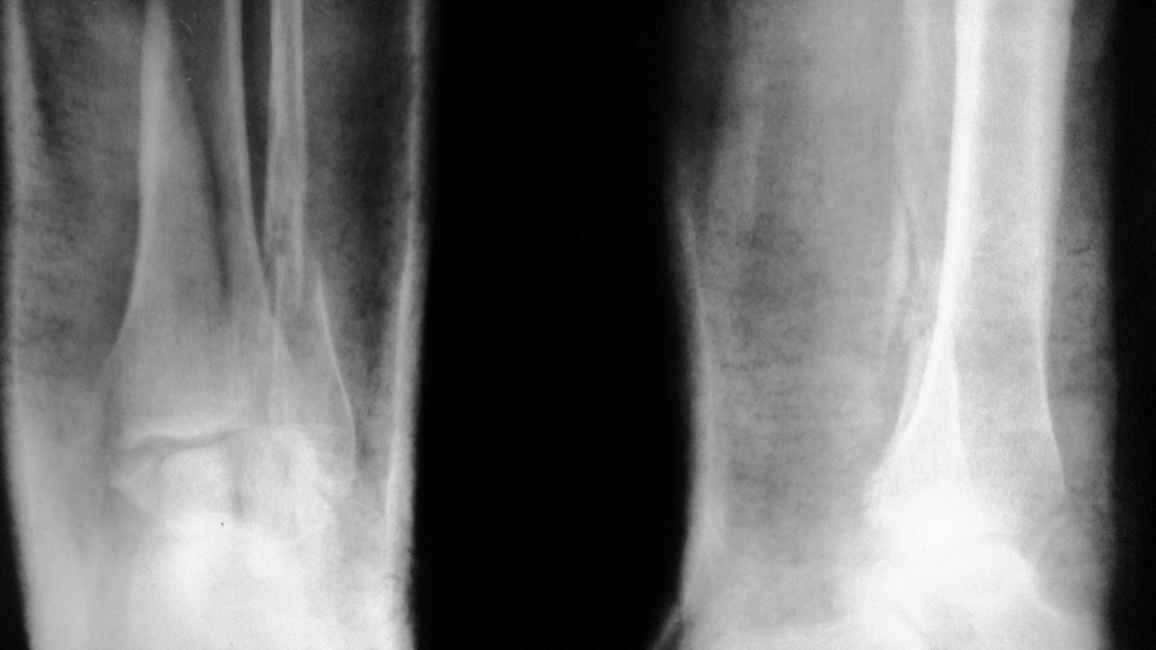

перелом внутренней лодыжки левой голени, левой м/берцовой кости с подвывихом стопы |

Уважаемые доктора!Мне срочно нужна Ваша консультация!Перелом оказался очень сложным,и, кажется упущено время.Всё ещё надеюсь на возможность консервативного лечения. 1 января подскользнулась и, упав, сломала ногу.В неотложке мне был наложен лангет.Живу в деревне, и в больницу добралась лишь25.01. Нога не беспокоила совсем.Но Р-грамма показала перелом внутренней лодыжки,м/берцовой кости с подвывихом стопы.Хирург выписал направление в вашу клинику на консультацию.Не представляю, как я смогу на костылях добраться к вам.Помогите пожалуйста хотя бы виртуальной консультацией!Снимки перешлю.Я в панике!

Действительно, взаимоотношения в суставе требуют восстановления. Добраться к нам проблем не составляет, привозят не то что ходящих на костылях, а и лежачих. Бывает, за тысячи км.